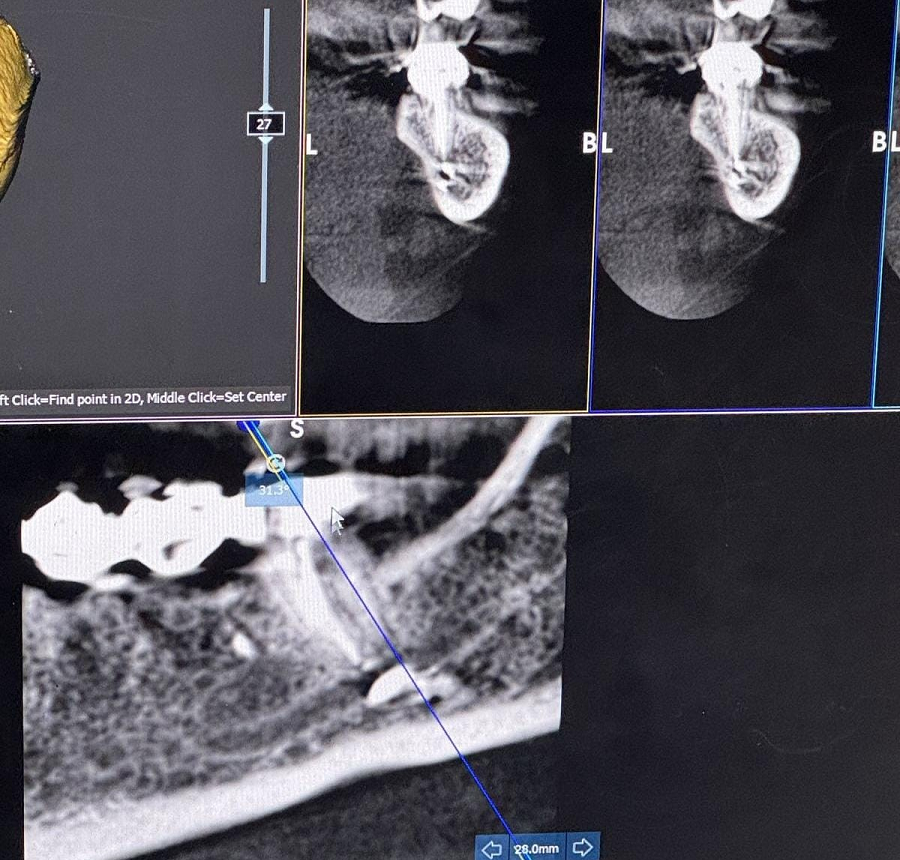

Hadisədən dərhal sonra üzümdə və dodaqlarımda hissiyyatsızlıq yarandı. Buna baxmayaraq, həkim vəziyyəti ciddiyə almaraq “yod çək, keçəcək” deyib, məni evə göndərdi. Bundan sonra vəziyyətim sürətlə pisləşdi. Digər tibb müəssisəsində təcili əməliyyat edərək həmin zərərli maddəni orqanizmdən xaric etdilər. Bir gün geciksəydim, sinir toxumamda daimi iflic riski yaranacaqdı. Hazırda üzümdə hissiyyat hələ tam bərpa olunmayıb, bunun uzun müddət davam edəcəyi bildirilib”.

R.Zaxarova bununla bağlı Səhiyyə Nazirliyinə müraciət etdiyini, lakin özəl müəssisə olduğu üçün məsələyə laqeyd yanaşıldığını deyib: “Bütün bu müddət ərzində məsuliyyət daşıyan tərəf mənə heç bir köməklik göstərmədi. Həkim məni başqa bir həkimə yönləndirəcəyini dedi, lakin onu da etmədi. Əlimdə rentgen görüntüləri və əməliyyat sənədləri var”.